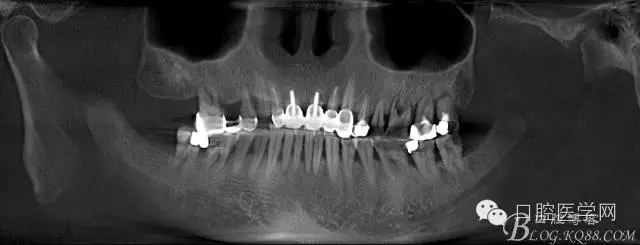

這是初診時候的CT片截圖。目標是14到16固定橋,別的牙齒先慢慢來,那么牙周肯定要做的,哪怕我要把14 16拔了,我也必須先去牙周科刮治。 在這里我感謝我們醫(yī)院的牙周科所有同事幫我們很多。刮治以后的牙齒拔掉即刻種植相對沒刮治過的牙齒肉芽會少很多,那么我在手術時候速度會快,會省力很多,我最討厭去刮很多肉芽,有時候搔刮肉芽的時間和精力比種牙的兩倍還多 而且很多肉芽會增加種植手術風險和術后反應最主要手術可以行云流水患者感覺良好 (我們一般會牙周治療和等待一段時間再約種植手術)者。

上圖14牙位和16牙位是我們想植入種植體的位置,考慮到47牙位還存在且沒有要拔掉的意思,那么我設計植體的時候適當往17牙位靠點。